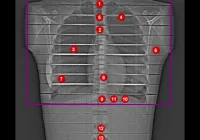

The primary challenge facing the field of radiomics is the lack of robustness and reproducibility. The variability in imaging acquisition and reconstruction parameters can significantly influence the derived radiomic features, leading to inconsistencies. In single-energy CT (SECT) systems, variations in factors such as the type of scanner, radiation dose, voxel size, and reconstruction algorithms can alter the radiomic features extracted from the same tissue. Dual-energy CT (DECT) systems, which acquire images at two different energy levels, add another layer of complexity. DECT techniques, including dual-source, rapid kV-switching, and dual-layer systems, can produce significantly different radiomic data, even when imaging the same object under similar conditions.

The development of photon-counting detector CT (PCD-CT) systems offers a promising avenue for enhancing the robustness of radiomics. Unlike traditional CT systems that convert X-rays into visible light before detecting them, PCD-CT systems directly convert X-rays into electrical signals. This direct conversion process reduces noise and improves spatial resolution, potentially leading to more accurate and reproducible radiomic features.

PCD-CT systems are particularly advantageous in low-dose imaging, where traditional CT systems may suffer from increased noise, thus compromising the reliability of radiomic analysis. The higher resolution of PCD-CT systems also allows for better characterisation of fine structures, which is crucial in diseases where subtle changes in tissue composition are clinically significant. However, the improved resolution also means that PCD-CT systems can detect minute differences that may not be clinically relevant, introducing variability in radiomic features.